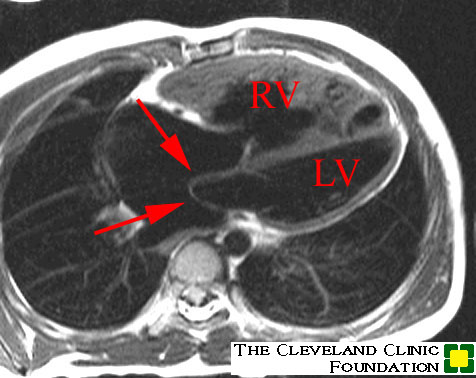

1- Bland-White-Garland

Syndrome: Anomalous origin of the left coronary artery (LCA)

from the pulmonary artery is a rare congenital anomaly accounting

for only 0.25-0.5% of all congenital heart defects [5,13]. It is

Infants typically present with failure to thrive, profuse sweating, dyspnea, and pallor [8]. The condition is one of the common causes of myocardial infarction and dilated cardiomyopathy in infants [7]. Without treatment, this anomaly most commonly results in death during early infancy (mortality rates of greater than 90% in the first year of life [7,15]), but survival into adulthood can occur if collateral coronary flow via the RCA is sufficient [8]. However, the risk for sudden cardiac death due to ischemic malignant ventricular dysrhythmia exits even in asymptomatic adult patients (sudden cardiac death occurs in 80-90% of cases) [5]. Treatment is surgical repair [5]- in infants this is done preferably using the coronary button transfer that produces the most anatomic correction and has excellent long-term results [8]. In adults, the preferred method is ligation of the LCA at its origin form the PA and placement of a CABG using the internal mammary artery or a saphenous vein graft [8]. In this syndrome, the LCA typically arises from the left inferolateral aspect of the main pulmonary artery just beyond the pulmonary valve [8].

Patients are generally noted to have an anterior wall ischemic perfusion defect and mitral insufficiency. An inferior/posterior perfusion defect may also be seen secondary to a right coronary artery to left coronary artery to pulmonary artery shunt.